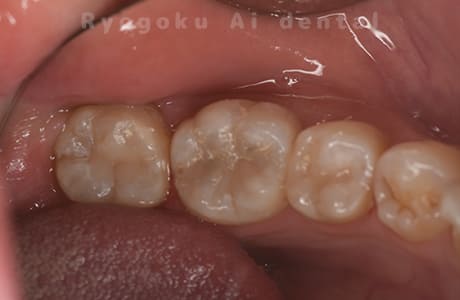

Case10

- 右下6番 重度カリエス

- 右下8を右下6へ移植に自家歯牙移植

- 約1か月半

- 220,000円

右下の銀歯が外れかかっているとのことでご来院された患者様です。虫歯が大きく、かつ歯が割れており、保存不可能と判断し、親知らずの移植を行いました。